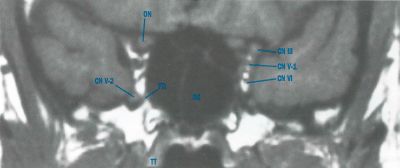

Anatomy

Key structures affected:

- Cavernous sinus

- Superior orbital fissure

- Orbital apex

Cranial nerves III, IV, VI, and the ophthalmic branch of V (V1), as well as other neurovasculature structures, traverse these regions, explaining the characteristic clinical features.

- The inflammatory process involves cranial nerves III, IV, V1, and VI, producing the hallmark ophthalmoplegia and pain. Involvement of the sympathetic fibers in the cavernous ICA or parasympathetic fibers that surround the oculomotor nerve (CN III) can also occur secondary to granulomatous inflammation.

Recent evidence supports the use of High resolution 3D skull base MRI with isotropic constructive interference in steady state (CISS) and 0.6-mm cut images with and without contrast as effective way to visualize cranial nerves and cavernous sinus lesions that were not previously visualized.[11]